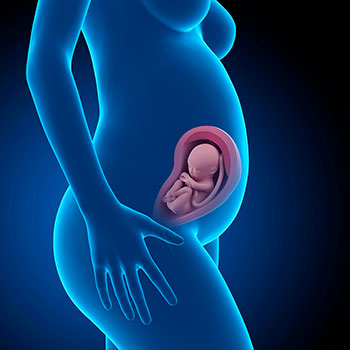

Na 29ª semana de gravidez, a tua barriga sobe e fica logo abaixo da tua caixa torácica. Isto, juntamente com a pressão das costelas, do diafragma, e do próprio útero, provoca um certo desconforto.

Na 29ª semana de gravidez, o bebé mede em média 38 centímetros desde o cocuruto até aos tornozelos e pesa cerca de 1,150 Kg.

Grávida de 29 semanas

A partir da 29ª semana vai começar a dar a volta e a colocar-se apoiado no colo do útero.